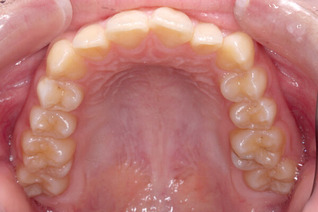

画像で見てみましょう。

画像では向かって右に見えるのが患者さんの左側です。

患者さんの右側(画像だと左側)よりもへこんでいるのがわかります。